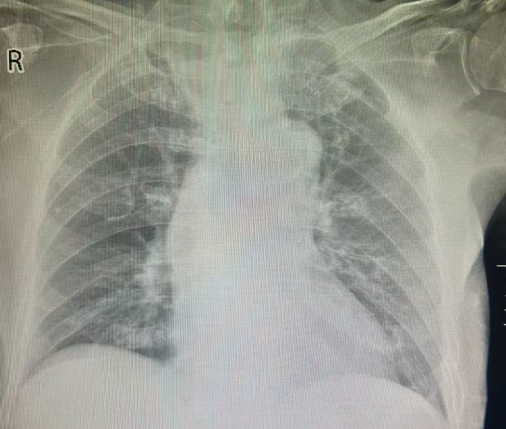

3、床旁胸片:

床旁仰卧位胸片,两肺纹理模糊,右中肺见结节状影,直径约 3 mm。肺门影增浓,卧位心影饱满,膈面光滑,双侧肋膈角未见明显异常。

图三:患者胸片(2025-8-22)